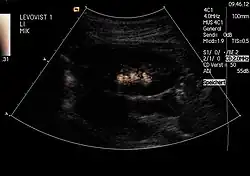

Um einen Rückfluss (Reflux) von Urin aus der Blase in die Niere auszuschließen: Diese Untersuchung, genannt Miktionsurosonografie (MUS), kann die bisher durchgeführte Röntgenuntersuchung mit Kontrastmittel (Miktionscystourogramm, MCU) ersetzen. Auf diese Weise ist also eine Refluxprüfung ohne Strahlenbelastung möglich. Da die empfindlichen Gonaden bei der Röntgenuntersuchung regelmäßig mit im Nutzstrahlenbündel liegen, ist dies ein großer Vorteil.

Um beim Jungen die Harnröhre mit darzustellen (da Jungen Harnröhrenklappen (Urethralklappen) haben können, Mädchen aber nicht), erfolgt die Erstuntersuchung beim Junge meist als klassisches MCU, Verlaufsuntersuchungen dann aber als MUS.